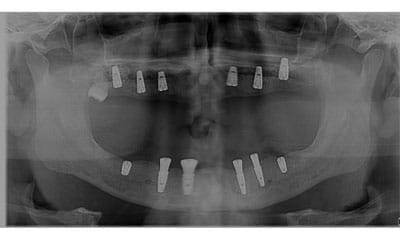

Transformări All-on-4 | All-on-6

Restaurarea funcționalității prin implantologie avansată. Radiografia confirmă ancorarea sigură, iar rezultatul final redă volumul natural al feței și un zâmbet radiant.